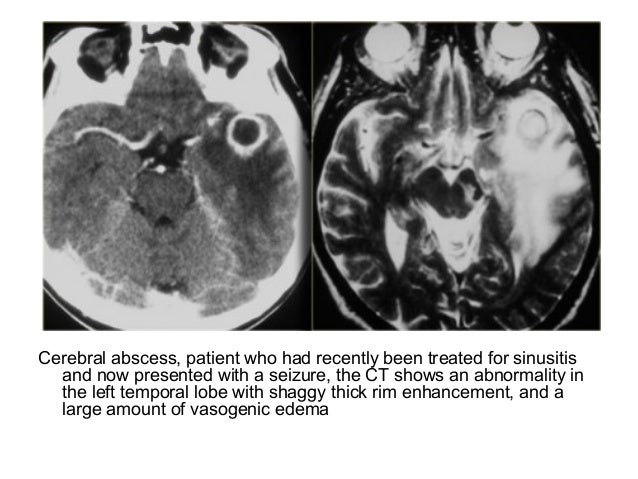

Sinusitis Imaging Overview Radiography Computed Tomography - Sinusitis Imaging Overview Radiography Computed Tomography